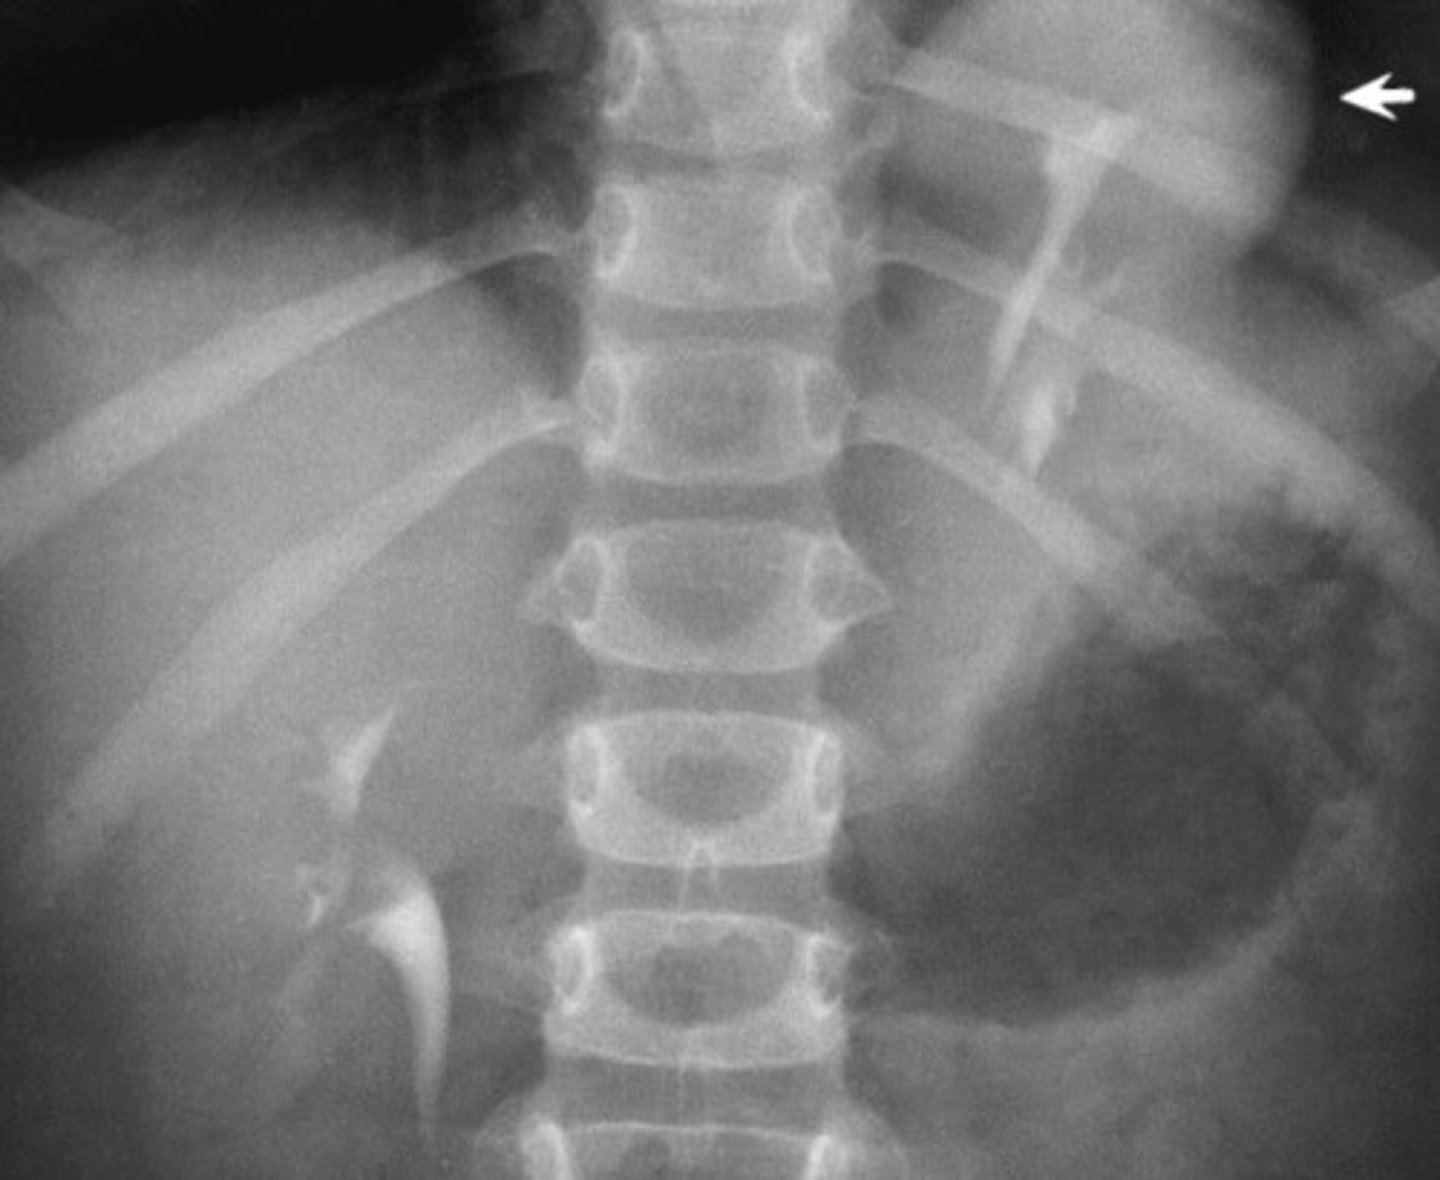

- Renal Agenesis

- Hypertrophic (bigger)

- 2

- What congenital anomaly is the absence of one kidney and ureter?

- How does the kidney that is present appear to compensate for the other not being there?

- How many renal arteries are present in the bottom radiograph?